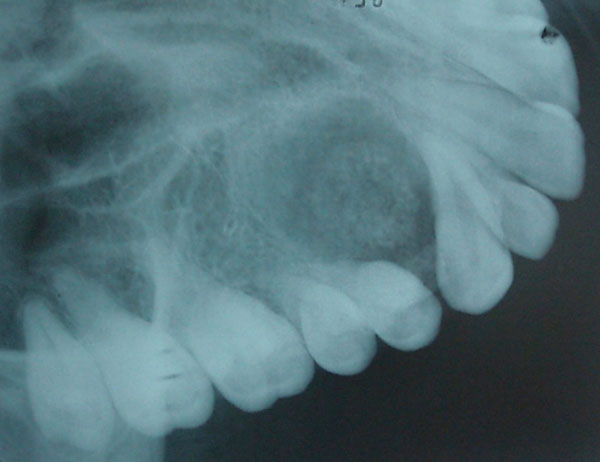

Fig. (2) Occlusal radiograph showing target like lesion between the roots of the canine and first premolar.